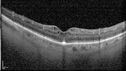

BRAO - plaques in vessels - GIF video of FA3 views78 year old female with vision loss for 1 week and old macular scar. Images show BRAO with plaques and FA shows occlusion.Oct 13, 2025